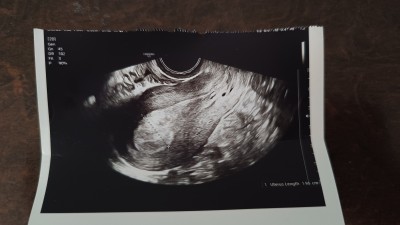

Dün beta hcg değerim 21küsür çıkmıştı akşam kanamam oldu değerim 2 küfürlere düştü. Hastanede alttan muanede bu görüntüyü aldılar anlayan yorumlanabilir mi?

Ultrasondan anlamıyorum ama canım kimyasal gebelik yaşamışsın bende 1 sene öncesi yaşamıştım kürtaj gerekmiyor bunda o yüzden korkma ben 1 sene sonra tekrar hamile kaldım şuan 30 haftalığım tekrar hamile kalırsın Allahın izniyle

Evet malesef benim için kötü bir deneyimdi. 2küsüre düştü ve kanamam şu an normal adete döndü. İki gün sonra tekrar beta baktırmaya gerek yoktur değil mi? Doktor gel demişti ama adette oldum. Kimyasal gebelik oluşup sonlandı diye düşünüyorum.